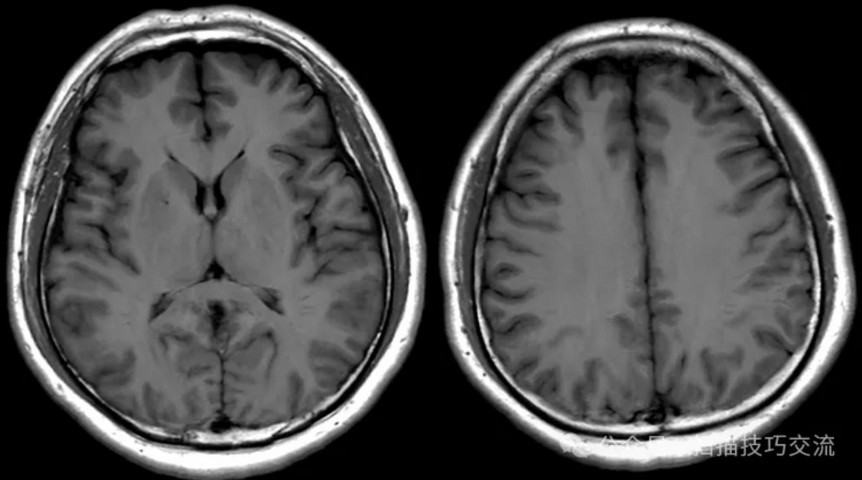

•汗腺分泌:正常,皮肤划痕正常反应。 •尿便障碍:无。性功能障碍无。 •专科情况:正常。不逐一罗列。 •辅助检查:01-05颅脑CT提示:1,上矢状窦、双侧横窦密度较高,请结合临床,必要时进一步检查;2,双侧脑室后角可疑稍高密度影,右顶叶局部脑沟密度可疑增高,建议进一步检查。 •初步诊断:静脉窦血栓

临床申请:颅脑平扫,静脉成像,磁敏感成像,颅内静脉血管黑血成像。

图像不逐一罗列,未见异常。